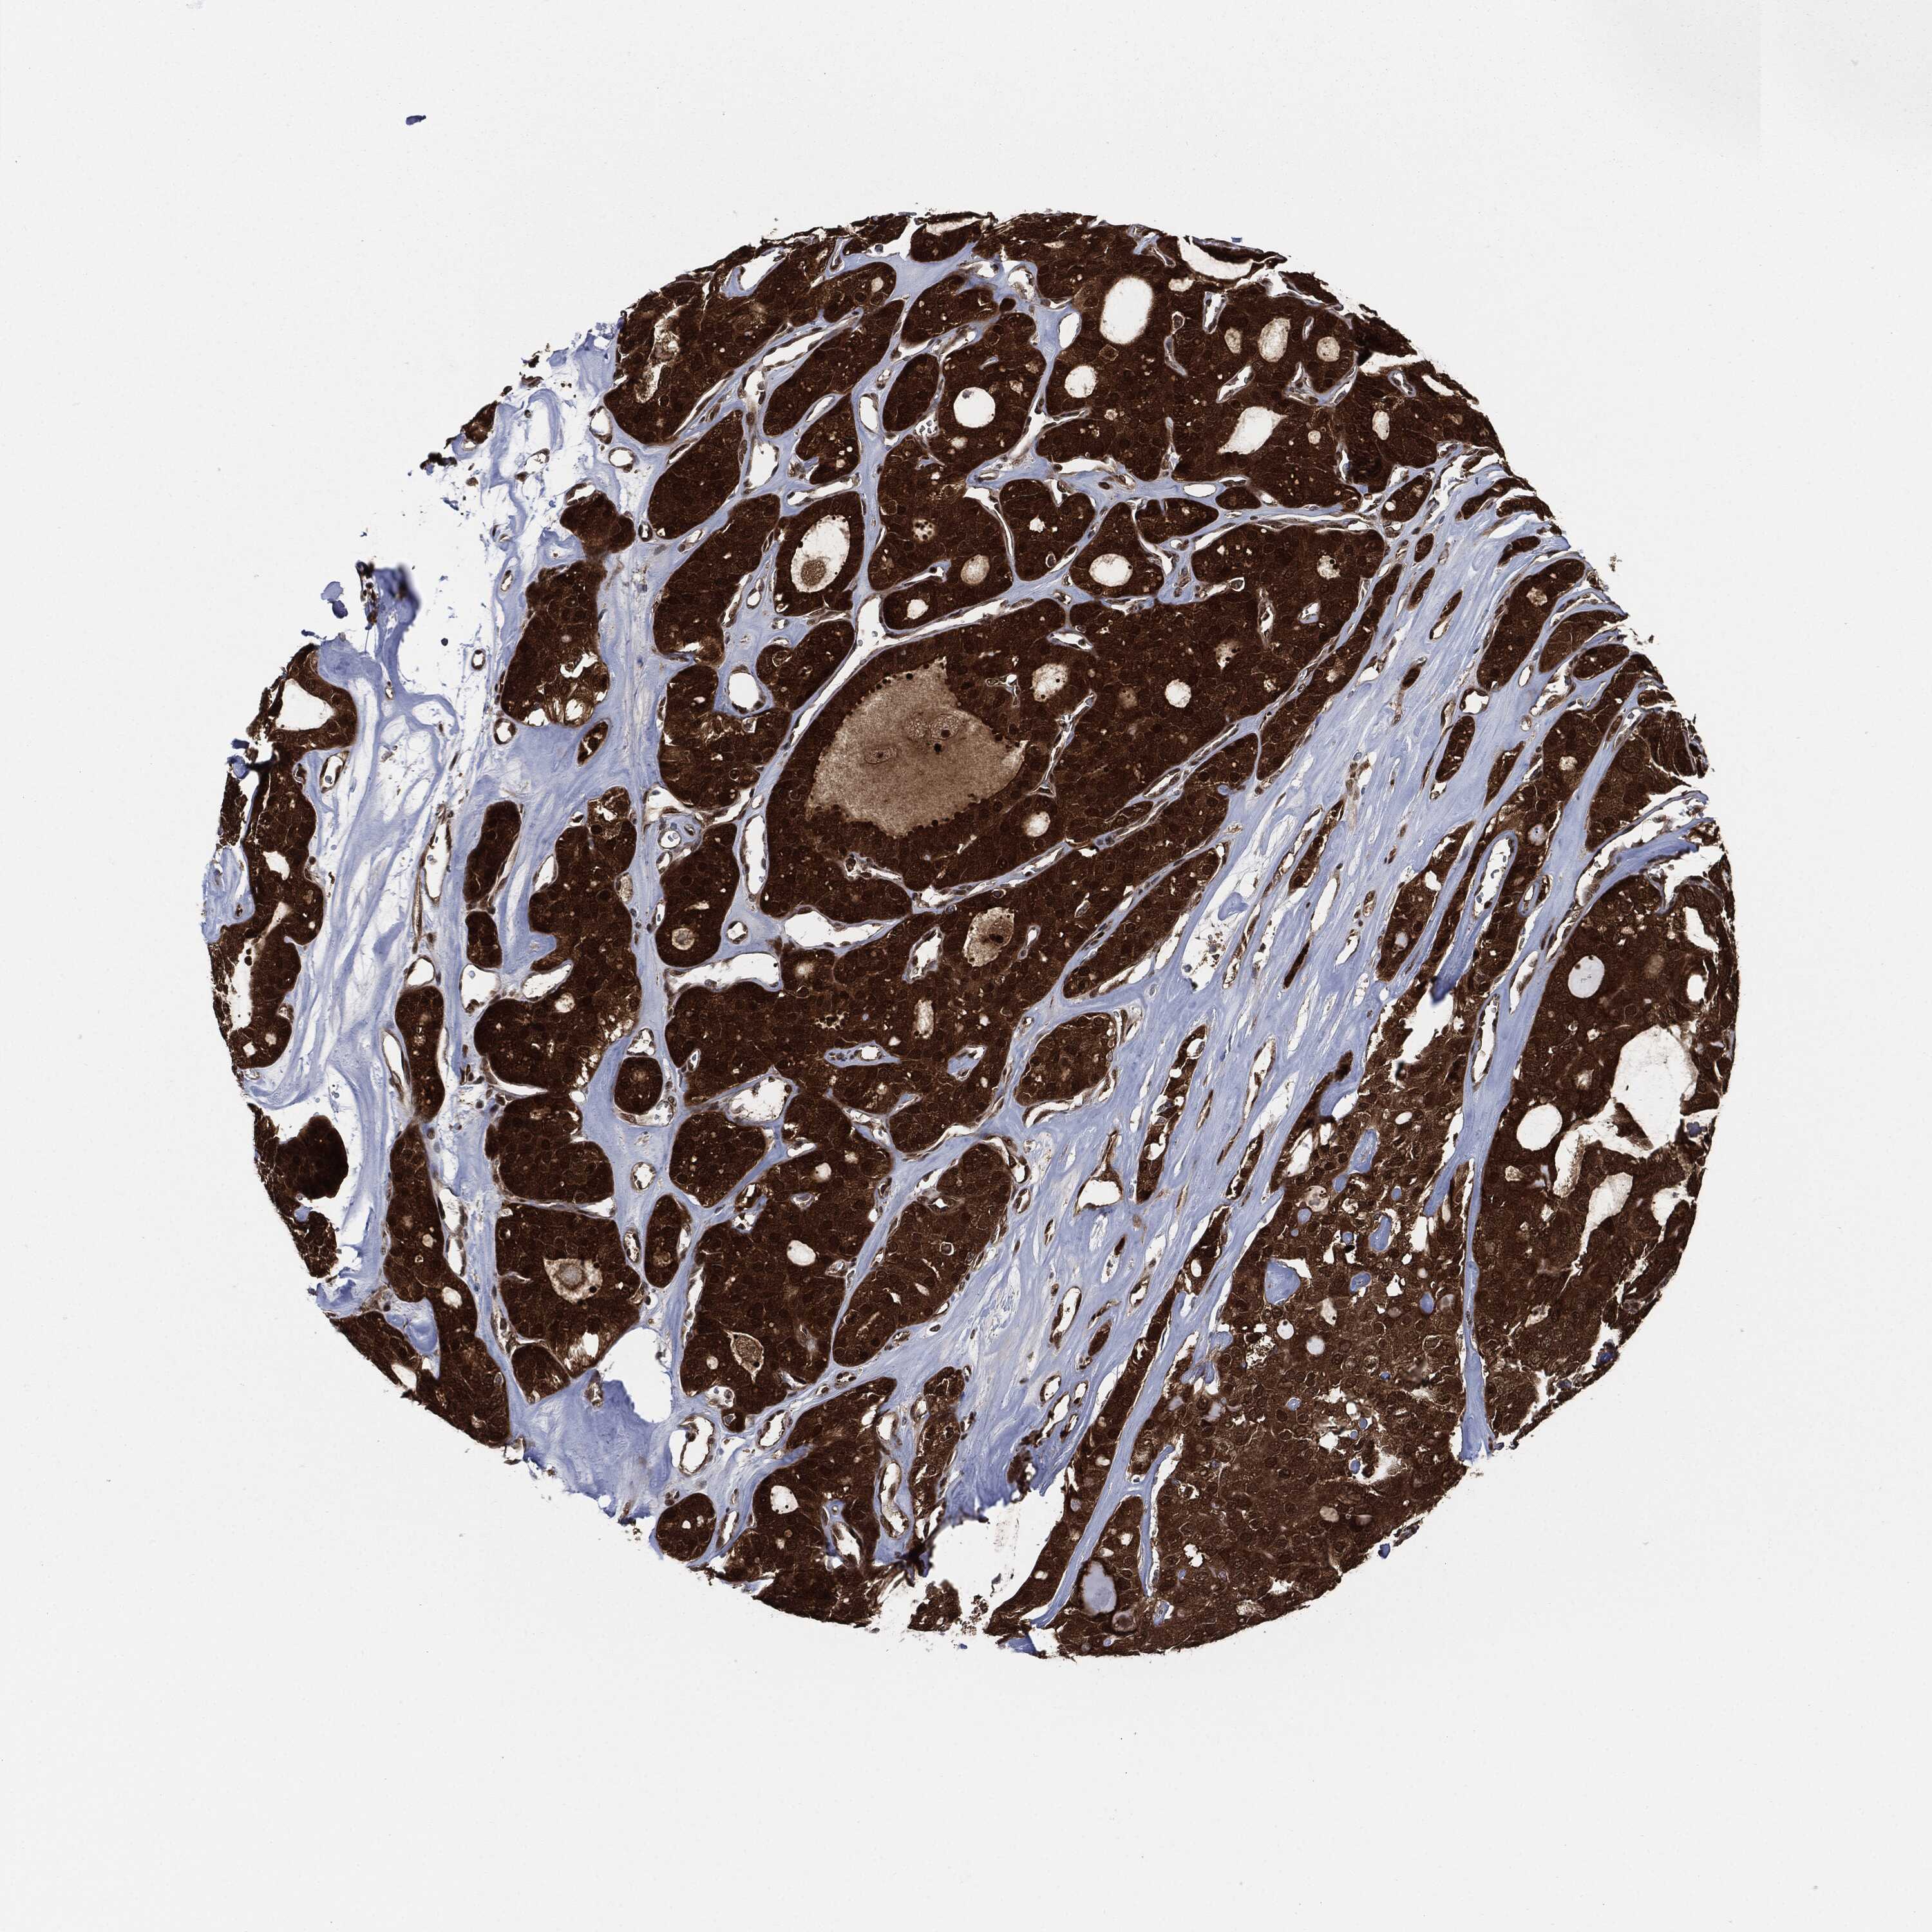

THYROID CANCER - Protein expressioni

A mouse-over function shows sample information and annotation data. Click on an image to view it in a full screen mode. Samples can be filtered based on level of antibody staining by selecting one or several of the following categories: high, medium, low and not detected. The assay and annotation is described here.

Note that samples used for immunohistochemistry by the Human Protein Atlas do not correspond to samples in the TCGA dataset.

Antibody stainingi

Antibody staining in the annotated cell types in the current human tissue is reported as not detected, low, medium, or high, based on conventional immunohistochemistry profiling in selected tissues. This score is based on the combination of the staining intensity and fraction of stained cells.

Each image is clickable and will lead to virtual microscopy that enables deeper exploration of all samples and also displays staining intensity scores, fraction scores and subcellular localization as well as patient and tissue information for each sample.

Antibody HPA034635

Staining

High

Medium

Low

Not detected

Intensity

Strong

Moderate

Weak

Negative

Quantity

>75%

75%-25%

<25%

None

Location

Nuclear

Cytoplasmic/membranous

Cytoplasmic/membranous,nuclear

Papillary adenocarcinoma, NOS

Follicular adenoma carcinoma, NOS